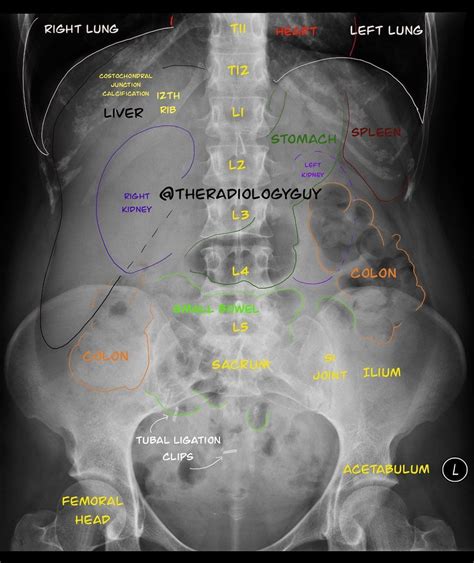

Interpreting the results of a Belly X Ray requires specialized training and expertise. Radiologists analyze the images to identify any abnormalities or signs of disease. Common findings include:

• Blockages or obstructions in the intestines.

• Fractures or dislocations of the spine or pelvis.

• Foreign objects, such as swallowed items or surgical instruments.

• Air or fluid in the abdominal cavity, which may indicate conditions like peritonitis or a ruptured organ.

Radiologists may also use the images to assess the size and shape of organs, such as the liver, spleen, and kidneys, to detect any abnormalities.